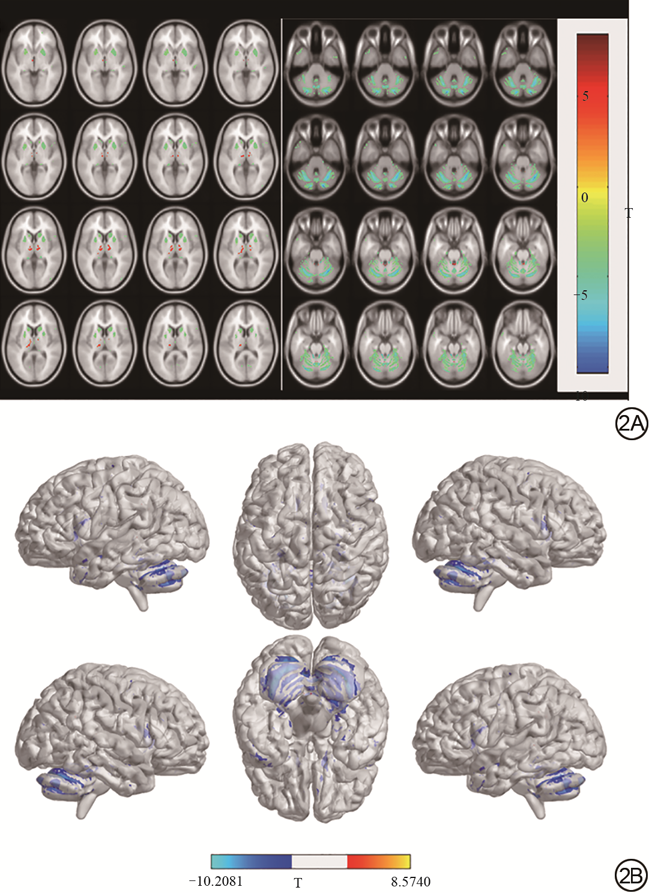

与HC相比,SCA3组的GMV显著降低,例如蚓部Ⅸ叶、双侧小脑、小脑下脚,尾状核、扣带回、额叶、海马体、中央前回、壳核、辅助运动区和颞叶、左侧距状裂周围皮层、中央旁小叶和海马旁回、右楔叶、梭状回和枕叶,尤其是小脑。但是,丘脑左侧板内核、背内侧核和右腹前核的GMV增加(表2,图2)。

与正常对照组相比,SCA3组神经量表评分MoCA(Z=-4.578,P<0.001)、MMSE(Z=-4.725,P<0.001)和RVR(Z=-5.773,P<0.001)的分数显著下降,ADL(Z=-6.447,P<0.001)和HAMD(Z=-5.285,P<0.001)分数显著升高。SCA3在小脑蚓Ⅸ叶、双侧小脑、尾状核、扣带回、额叶、海马体、中央前回、壳核、辅助运动区和颞叶、左侧距状裂周围皮层、中央旁小叶和海马旁回、右楔叶、梭状回和枕叶存在体积萎缩(P<0.001,FDR校正);体积增加的为丘脑左侧板内核、背内侧核和右腹前核(P<0.001,FDR校正)。差异脑区体积与神经心理学量表偏相关性分析显示:共济失调等级表(Scale for the Assessment and Rating of Ataxia, SARA)和国际合作共济失调评分表(International Cooperative Ataxia Rating Scale, ICARS)评分与蚓部Ⅸ小叶、双侧小脑、中央前回、颞叶、左侧距状裂周围皮层、右侧尾状核、扣带回、额叶、梭状回和枕叶呈负相关,与左侧丘脑板内核呈正相关;MoCA评分与蚓部Ⅸ小叶和双侧小脑呈正相关;ADL评分与双侧小脑、左侧距状裂周围皮层、颞叶、右梭状回和蚓部Ⅸ小叶呈负相关;HAMD评分与双侧小脑、右额叶、左颞叶呈负相关;RVR评分与双侧小脑、右额叶、左颞叶和蚓部Ⅸ小叶呈正相关。